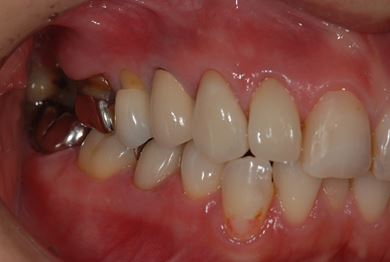

| 主訴 | 現在痛みはなく、前歯の汚れを治したい。奥歯はブリッジを考えている。審美を考えているが、今治療をしたいというよりは、セラミックなど詳しいことがわからないので、計画や説明を伺いたい。 | ||||||||||||||||||||||||||||||||

| 治療方針 | 上前歯部分、セラミック治療にて審美的回復を行う。 | ||||||||||||||||||||||||||||||||

| 治療内容 | オールセラミッククラウン3本(オールセラミック用土台3本)、メタルボンドセラミッククラウン1本 | ||||||||||||||||||||||||||||||||